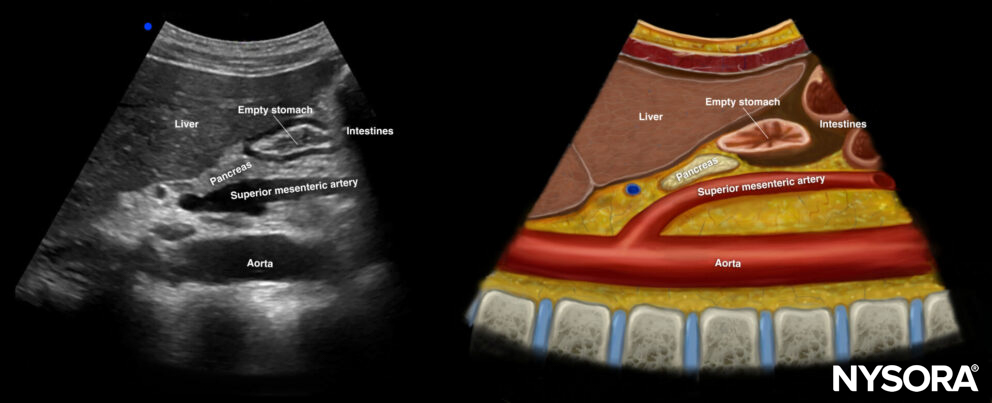

Empty stomach

In case of an empty stomach, the antrum has a typical round-shaped or elliptical structure which is often referred to as the bull’s eye pattern. The structural pattern differentiates itself from other structures by a thick hypoechogenic wall built out of muscularis propria with central and external hyperechoic layers, the mucosa, and serosa.

Ultrasound and Reverse Ultrasound Anatomy of an empty stomach.